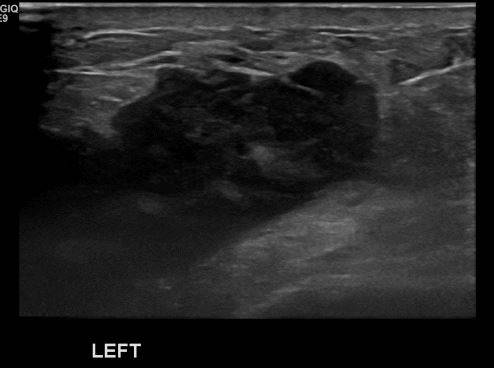

상기환자 좌측 유방의 멍울로 내원하신 60대 여성분으로 좌측 만져지는 멍울

조직검사 시행하여 좌측 침윤성 유관암 진단되었습니다.